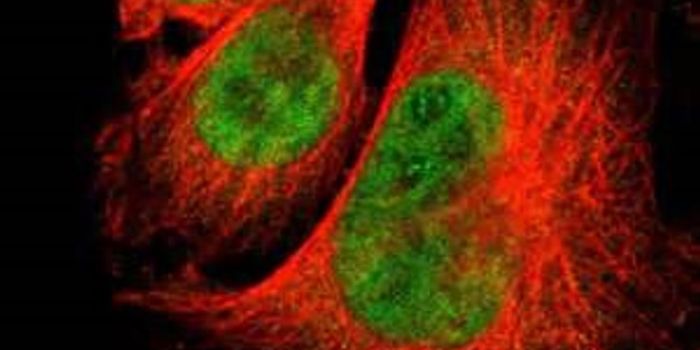

NOV 10, 2017CancerBy carefully observing how DNA is packaged inside of cancer cells, scientists have developed a therapy that they say can ...